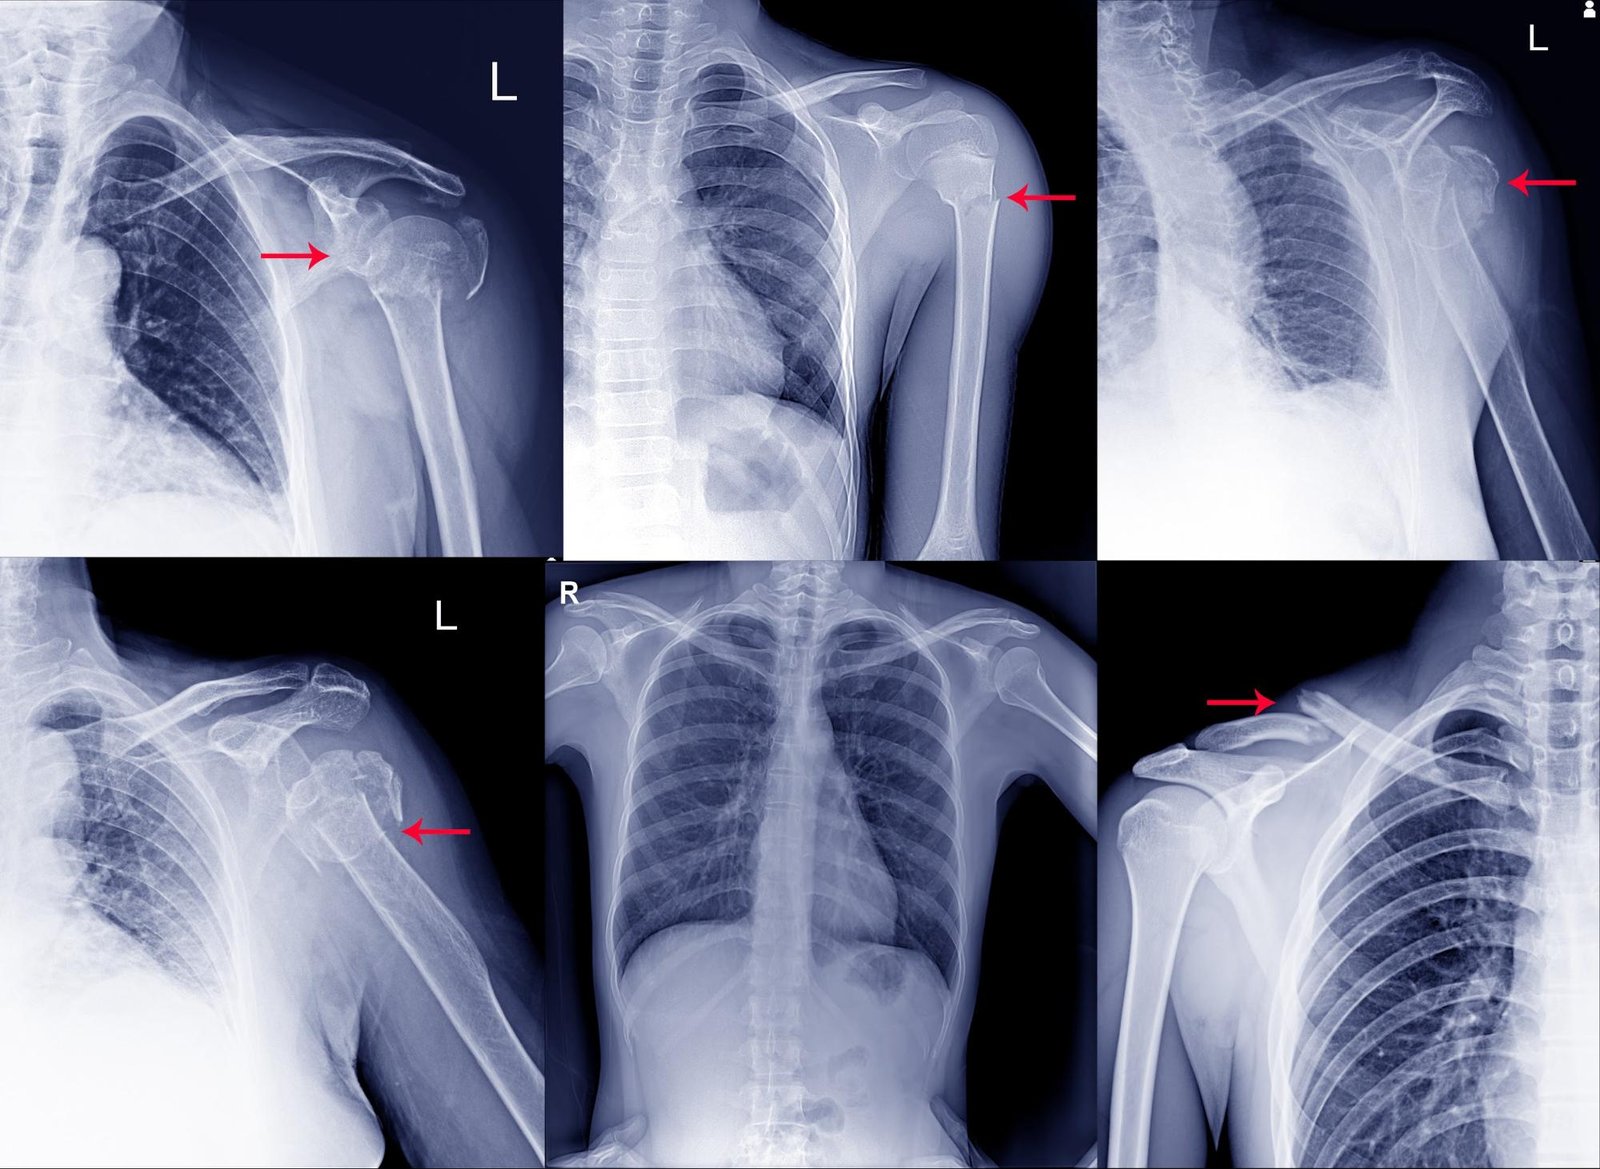

Several X-ray results showing different shoulder injuries

Slip and fall cases are premises liability claims. This means that your claim is against the owner or controller of the property where you were injured.

First, gather your treatment records. You’ll need medical bills and other documents showing your prognosis. This includes the results of tests and procedures showing how and where your shoulder was injured.

Some common diagnostic tests for shoulder injuries are:

• X-rays

• MRI

• Range-of-motion tests

• Strength/resistance tests with both affected and unaffected shoulders